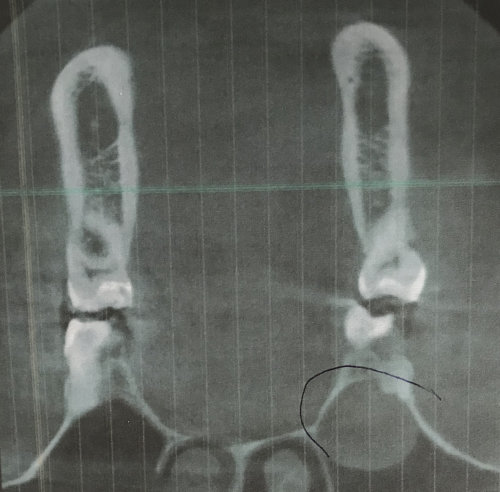

После снятия брекетов носил пластинку около 1 год 5 месяцев на ночь. К вечеру чувствовал, что пластинка садится туго, к утру все нормально. В 15 лет заметили, что прикус открытый. Сделали панорамный снимок. Определили, что 8-ки неправильно расположены в челюсти.

Через полтора года сделали еще один панорамный снимок, корни уже почти сформированы. Все стоматологи говорят, что нужно удалять 8-ки. Еще есть КТ. Сегодня были на консультации у стоматолога-хирурга. Он сказал, что очень сложно, но можно удалить пока один зуб снизу слева. Верхние предложил пока не трогать, подождать, когда они ближе подойдут.

Нужно ли удалять 8-ки (сейчас внизу)? Что делать с верхними 8-ми? Может ли удаление 8-ок немного расслабить зубной ряд, и хоть как то улучшить прикус?

В обязательном порядке требуется повторное эндодонтическое лечение. Восьмые зубы удалять надо, но, важно определить, не расположены ли верхние на границе с верхнечелюстной пазухой, а нижние в нижнечелюстном канале. Определить это можно по трехмерному снимку. Если зубы лежат в области этих анатомических образований, то необходимо подождать и провести удаление позже. Но требуется коррекция открытого прикуса.